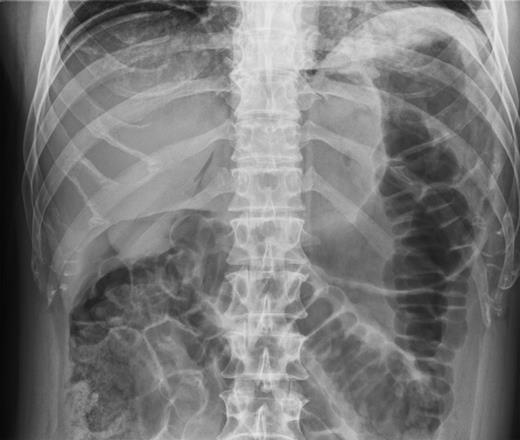

In 2011, a 46-year-old man presented with an acute abdomen. Patient had a 3 day history of abdominal pain with dyspepsia, initially epigastric with pain radiating to his shoulder. He had no associated symptoms of nausea, vomiting or change in bowel habit. There was no history of peptic ulcer disease, inflammatory bowel disease, diverticular disease or malignancy. His pain was refractory to standard analgesics and exacerbated by movement and palpation of the abdomen. There was no past medical or family history of note, and the patient had never experienced these symptoms before. Routine observations were normal, except for tachycardia. On examination, there were no peripheral stigmata of inflammatory bowel disease, abdomen was diffusely tender and tympanic, but soft with normal bowel sounds. Blood tests showed no significant abnormalities, and C-reactive protein (CRP) levels were not measured. Plain abdominal and erect chest radiographs showed pneumoperitoneum (Fig. 1) with Rigler's sign present around small bowel loops lower in the abdomen (Fig. 2).